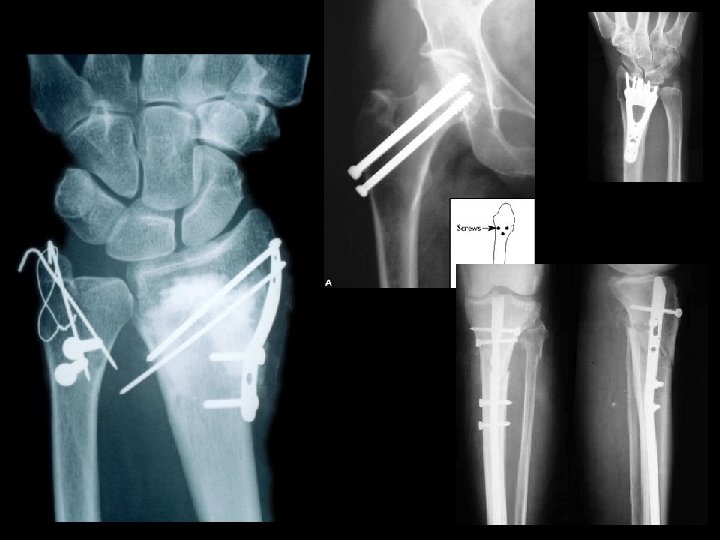

Internal Fixation

External Fixator

Ilizarov and external fixator